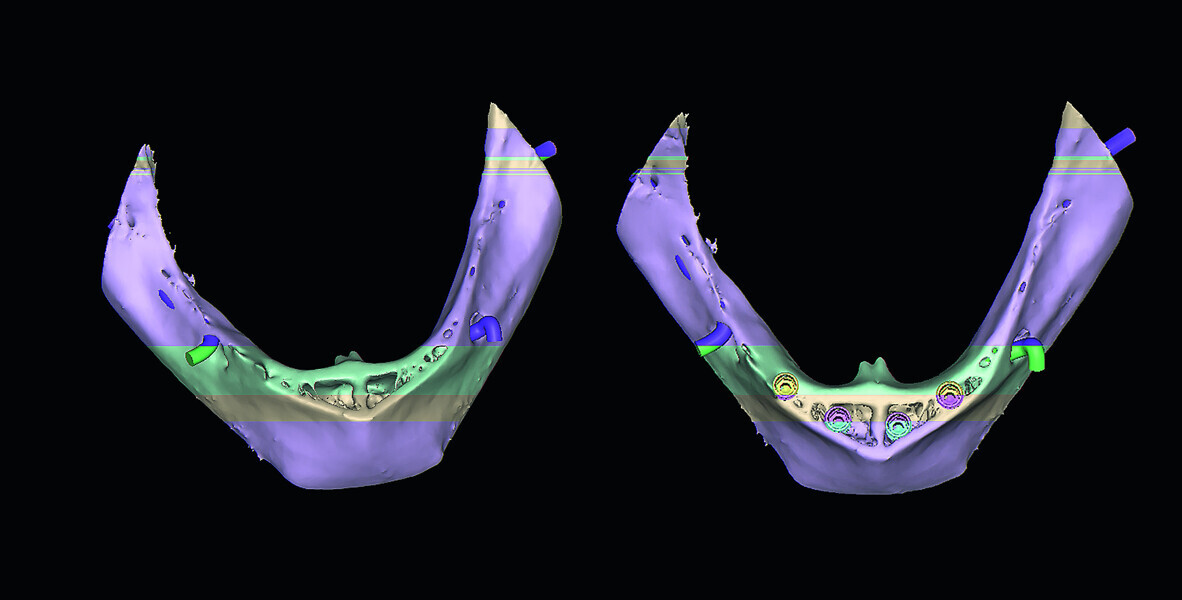

Fig. 10: The cross-sectional slices revealing ‘hollow’ areas in the symphysis.

Fig. 11a: The ‘clipping’ view with simulated implants reveals ‘hollow’ areas in the symphysis.

Fig. 11b: The ‘clipping’ view with simulated implants reveals ‘hollow’ areas in the symphysis.

Fig. 12: The mandibular 3-D reconstructed volumes illustrating the hollow areas and potential implant receptor sites.